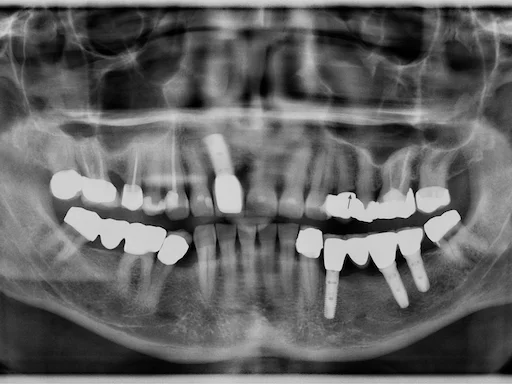

Patientenfall: Zähne 44,45,46,48 - Röntgenaufnahme

Schritt 1

Dieser Patientenfall aus unserer Praxisklinik in Herne spiegelt die moderne Zahnmedizin in vollem Umfang wider.

Patientenfall: Zähne 44,45,46,48 - Planung

Schritt 3

Die Planung dieses Eingriffs erfolgte voll digital über ein DVT (Volumentomographie), wodurch präzise Daten für die Behandlung erhalten wurden. Die Informationen wurden mithilfe der Software SIM Plant in eine maßgeschneiderte Bohrschablone überführt, was eine exakte Implantation ermöglicht.